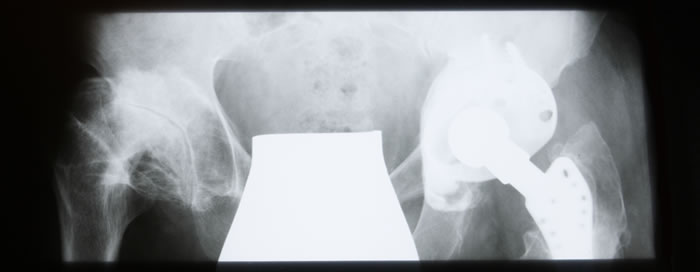

Therapien Fachärztliche Behandlung Orthopädische Erkrankungen sind fast immer mit Schmerzen verbunden. Erfahren Sie mehr über die therapeutischen Möglichkeiten in unserer Praxis für Orthopädie. Akupunktur Die Akupunktur ist ein wichtiger Praxisschwerpunkt, da gerade orthopädische Leiden und Funktionsstörungen sehr gut auf Akupunkturbehandlungen ansprechen. Osteopathie Unsere Praxis ist ein zertifiziertes Schwerpunktzentrum für Osteoporose. Behandlung in drei Schritten. 2. und 3. Säule: sog. Basistherapie und spezifische medikamentöse Osteoporosetherapie. Therapie der Osteoporose Unsere Praxis ist ein zertifiziertes Schwerpunktzentrum für Osteoporose. Behandlung in drei Schritten. 2. und 3. Säule: sog. Basistherapie und spezifische medikamentöse Osteoporosetherapie. Chirotherapie Durch gezielte Handgriffe können wir, als speziell ausgebildete Ärzte für Chirotherapie, das Gelenk lösen. Chirotherapie ist eine beliebte Behandlungsmethode, da häufig sofortige Schmerzlinderung eintritt. Stoßwellentherapie Extrakorpurale Stoßwellentherapie (ESWT): Therapeutisch eingesetzte gebündelte Schallwellen (Stoßwellen), z.B. zur Behandlung von „Kalkschulter“, Tennis-, Golfer-Ellenbogen. Arthrosetherapie Arthrosetherapie, z.B. Hyaluronsäure-Therapie: Der im Alter fortschreitende Gelenkverschleiß ( Arthrose ) muss nicht in einer Operation oder mit einem künstlichen Gelenk enden. Hochtontherapie Die Hochtontherapie ist eine innovative Weiterentwicklung der klassischen Reizstromtherapie und wird der physikalischen Therapie zugeordnet. Diese Energie sind mittelfrequente Ströme zwischen 4000-32000 Hertz. Kinesiotape Einfach anmutende aber effektive Methode zur Schmerztherapie. Erfunden wurde diese Behandlungsmethode durch den Japaner Dr. Kenzo Kase Ende der 70er Jahre. Laser Laser durchdringt alle Gewebeschichten und aktiviert Regulationsvorgänge sowie Stoffwechselprozesse in den Zellen. Damit ist die Behandlung auch tiefer gelegener Krankheitsherde möglich. Operationen Ambulante und stationäre Operationen führen wir im St. Josef-Krankenhaus in Engelskirchen durch: Arthroskopien der großen Gelenke, endoprothetischer Ersatz.